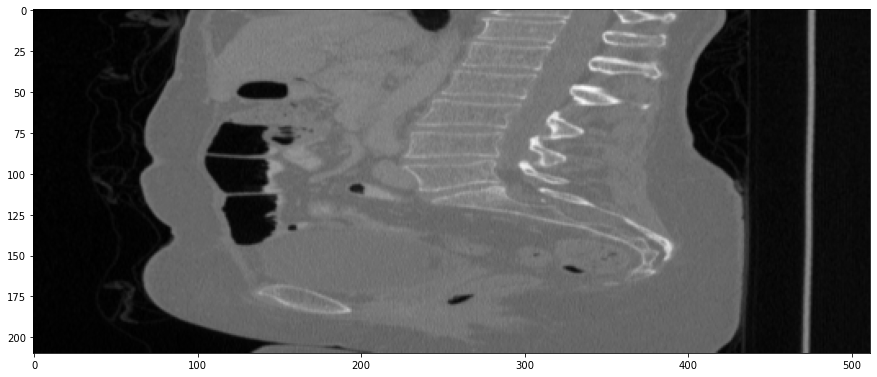

Refer to caption

(a) True Thick-slice image

(b) Simple Averaging

RMSE: 0.0250, PSNR: 38.0530

(c) Gaussian Averaging

RMSE: 0.1758, PSNR: 21.1182

(d) Direct Downsampling

RMSE: 0.0348, PSNR: 35.1697

(e) Proposed Simulation

RMSE: 0.0051, PSNR: 51.8504

Figure 3: Coronal-plane thick-slice image quality comparison across four simulation methods.

The results from all conducted experiments, represented as mean ±plus-or-minus\pm standard deviation, are tabulated in this section. We assessed the performance of our proposed simulation method against Simple Averaging, Gaussian Averaging, and Direct Downsampling. This was accomplished by simulating images with a thickness of 3mm from those with a thickness of 1mm, utilizing the 2016 Low Dose CT Grand Challenge dataset. The results outlined in Table III provide a comparative analysis of different thick-slice simulation methods used in two datasets from the 2016 Low Dose CT Grand Challenge. Both the PSNR and the RMSE were used as key performance indicators for these methods. The data clearly demonstrate that the proposed method significantly outperformed Simple Averaging, Gaussian Averaging, and Direct Downsampling in both datasets (D45 and B30). The highest PSNR values were obtained with the proposed method, yielding 49.7369 ±plus-or-minus\pm 2.5223 and 48.5801 ±plus-or-minus\pm 7.3271 for D45 and B30 datasets, respectively. The proposed method also registered the lowest RMSE with values of 0.0068 ±plus-or-minus\pm 0.0020 and 0.0108 ±plus-or-minus\pm 0.0099 for D45 and B30, respectively. These results indicate a superior level of accuracy and reliability in the proposed method. The statistically significant differences were confirmed by a Wilcoxon signed-rank test with p-value ¡ 0.05, implying that the improvements from the proposed method were not due to random chance. These findings support our first hypothesis that the proposed simulation method provides a more efficient and precise approach to thick-slice simulations compared to traditional methods. To provide a more comprehensive evaluation, visual comparisons from axial, coronal and sagittal plane were also undertaken, as depicted in Figures 2 to 4. In summary, Our proposed method demonstrated substantial enhancements in terms of both PSNR and RMSE, indicating a distribution more closely aligned with the authentic thick-slice image.